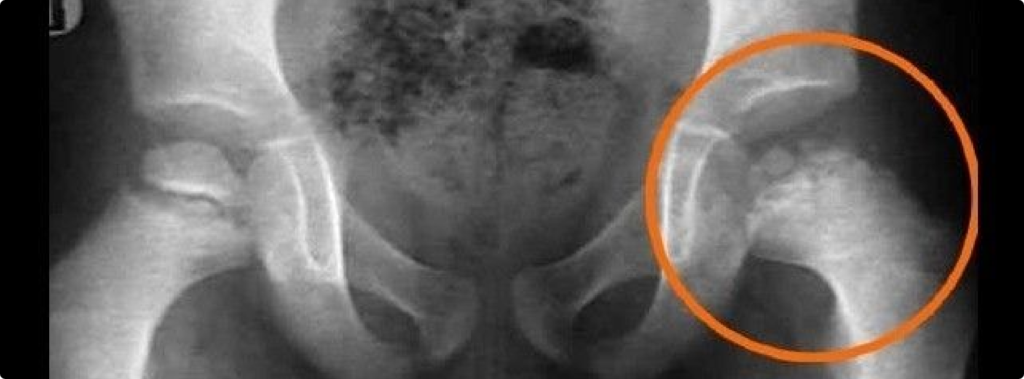

Epifisiólise do Fêmur Proximal